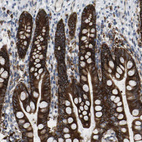

Immunohistochemical staining of human Testis shows strong membranous and granular cytoplasmic positivity in cells in seminiferous ducts.